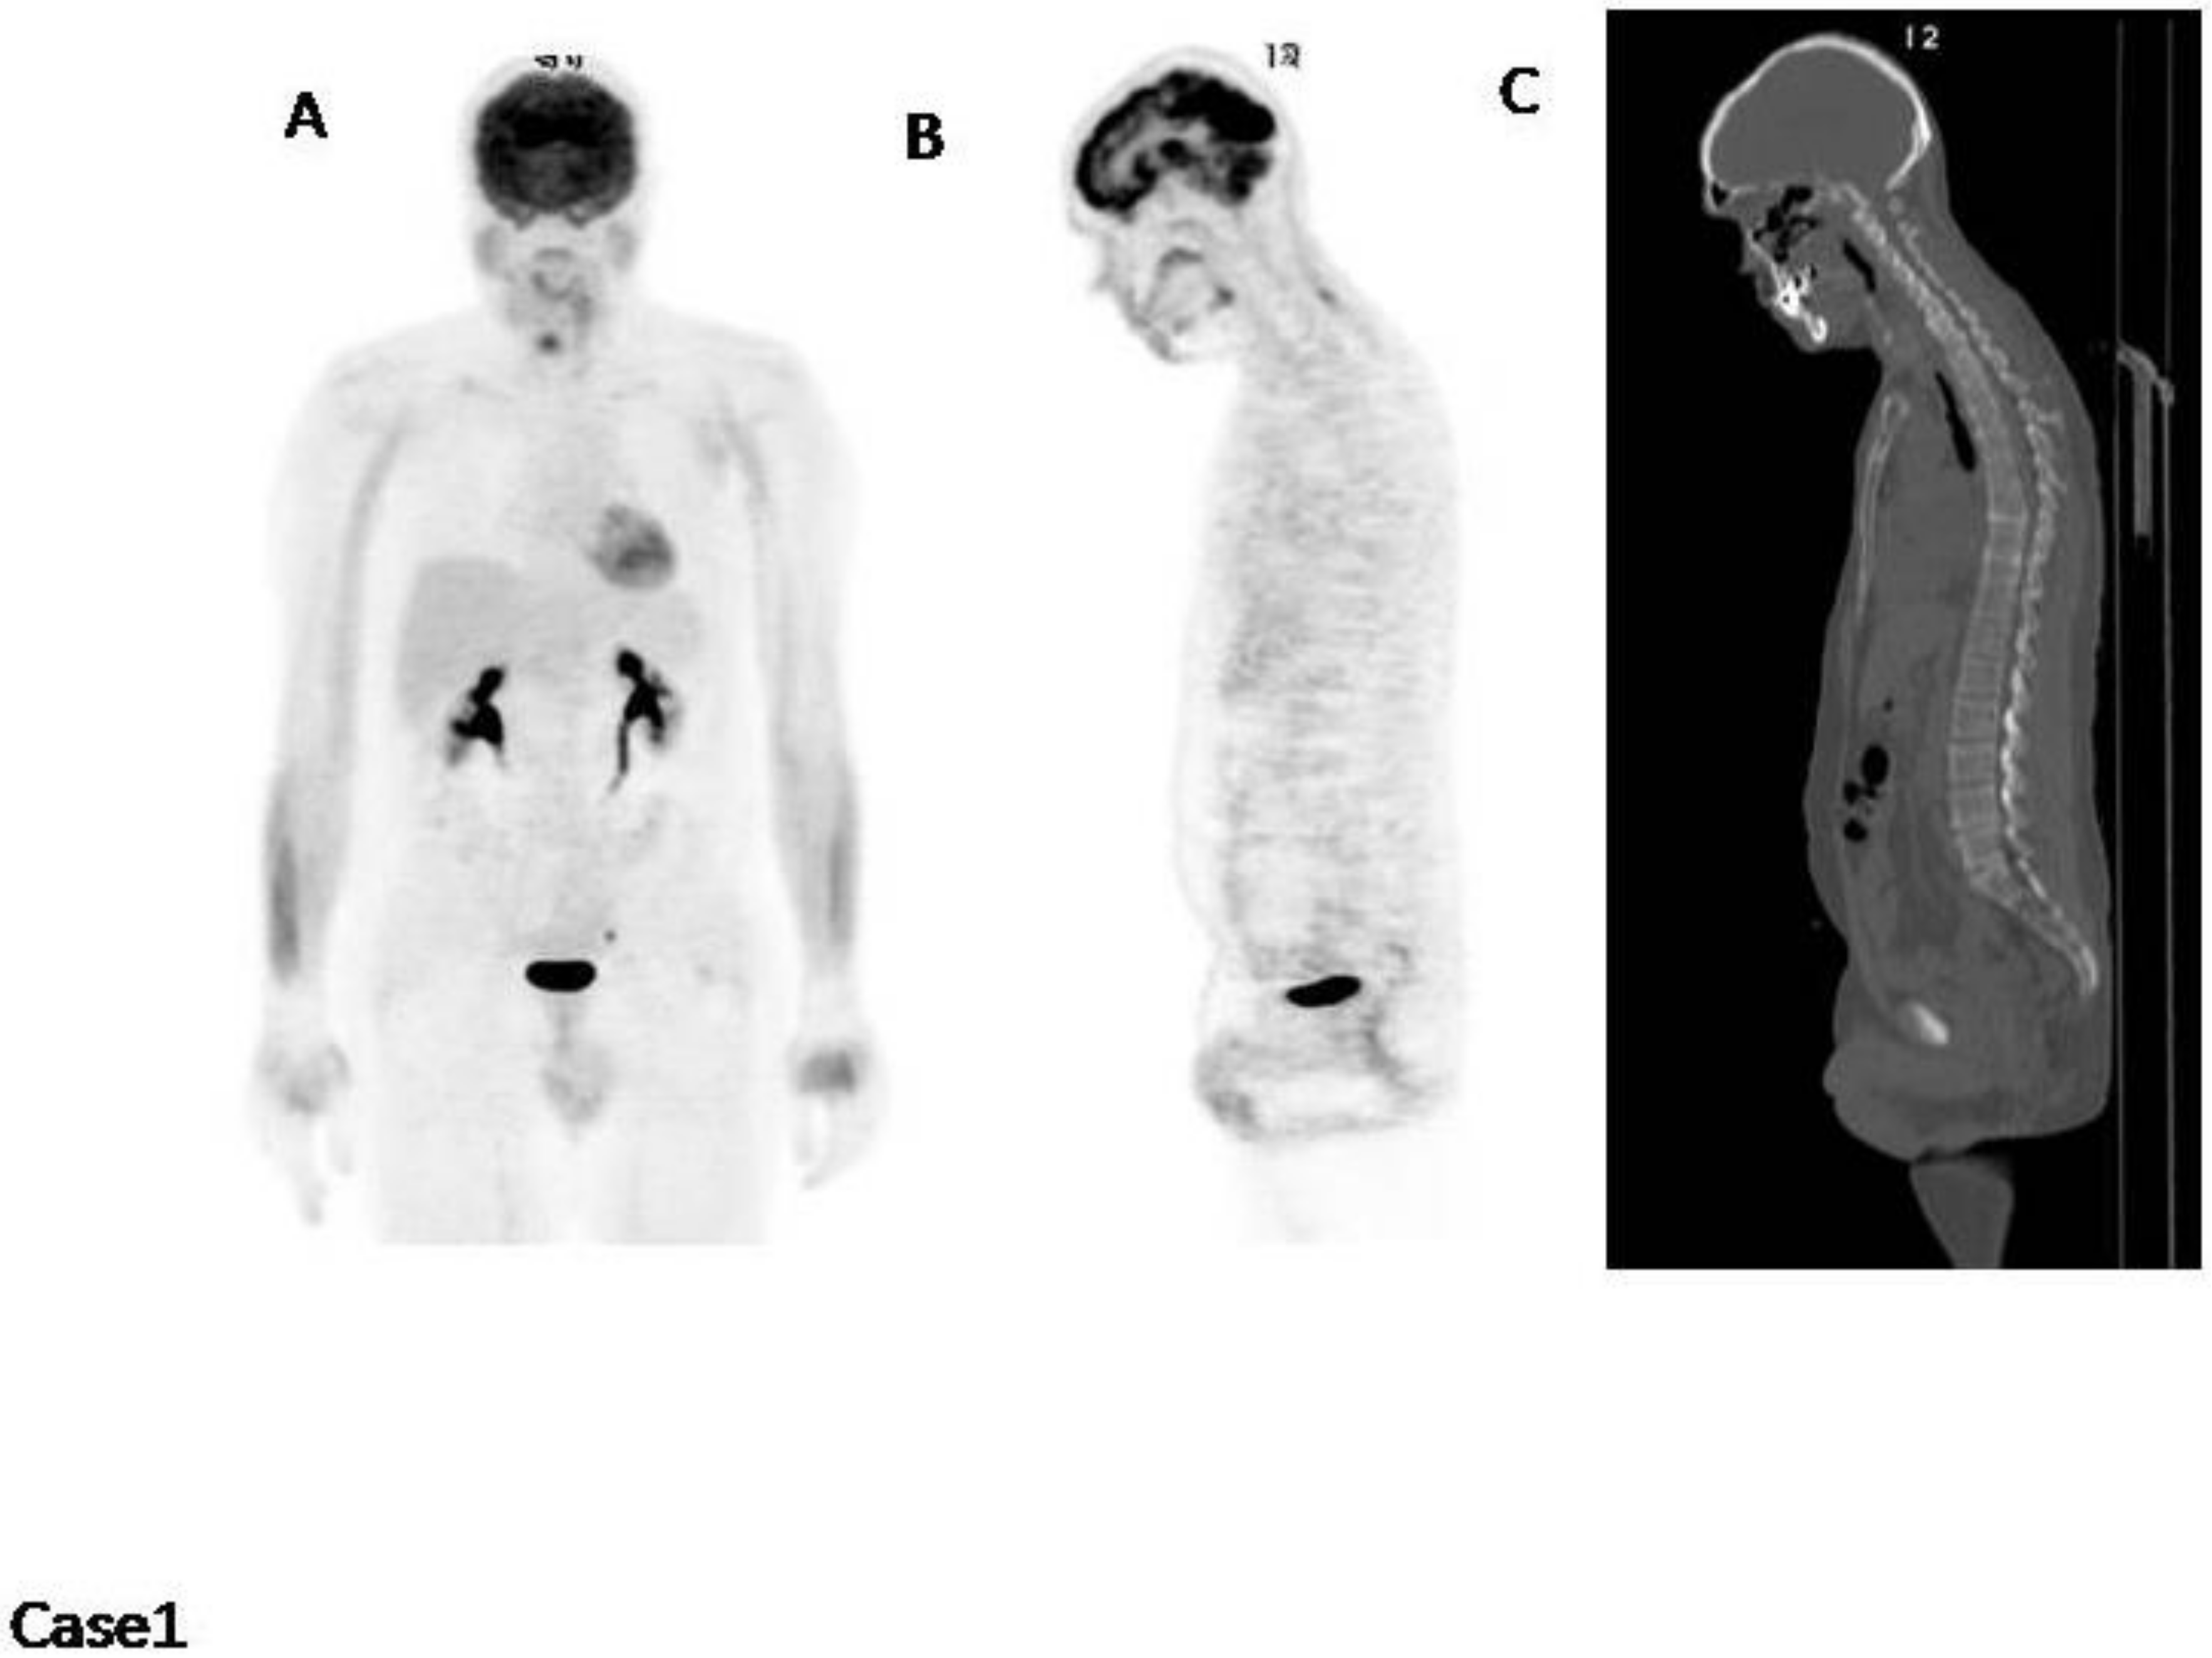

4. Impetus Criteria: Examples of Application